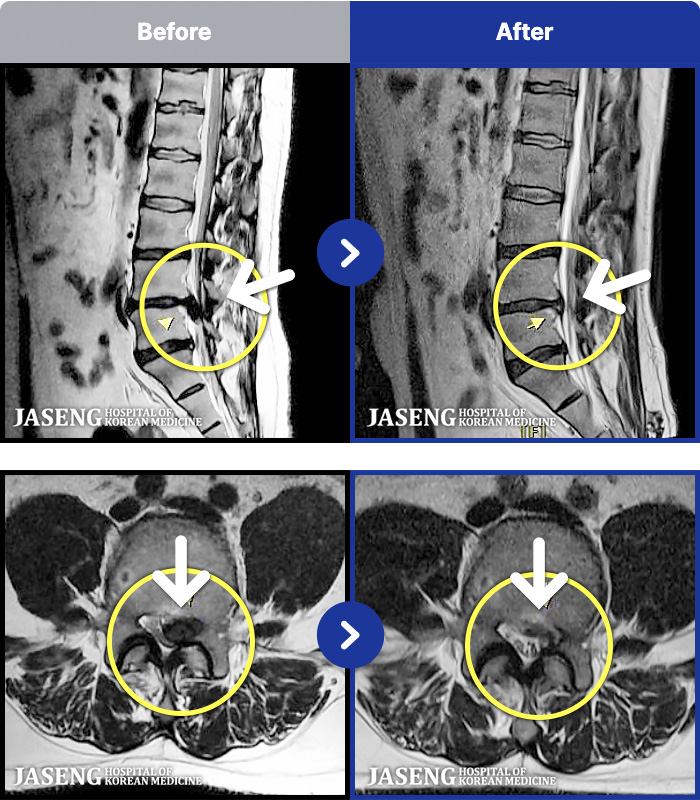

94 MRI ũ ʸ Ȯϼ.

ȯںп Ǹ ǿ ԿǾ, ο ġ ۿ Ƿ ġḦ Ͻñ ٶϴ.